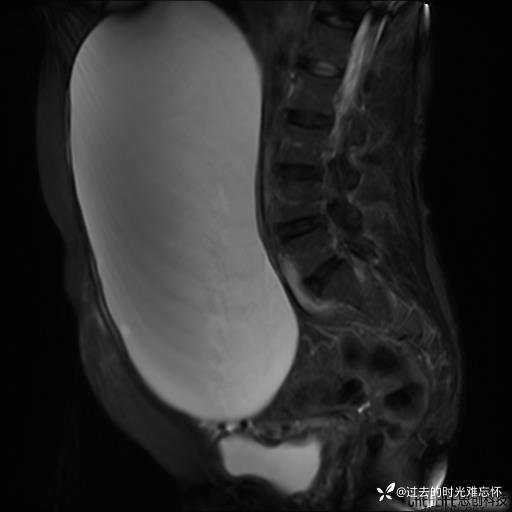

腹大能容5000液;术后腹部好轻松。妙手回春有结果。公布结果。

患者性别:女

患者年龄:65岁

主诉: 发现腹部隆起半年余。无其他明显不适。

浆液性囊腺瘤 (22)